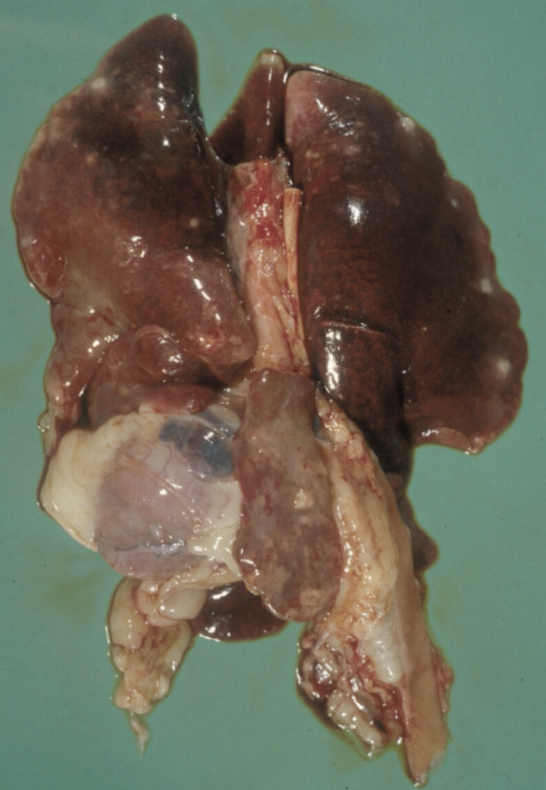

如果在没有明确诊断的情况下实施安乐死,强烈建议进行死后检查,且进行起来相对简单。这样既可以评估与FIP一致的总体变化(图2 ),也可以取样进行组织病理学检查。如果经济限制排除了后者,则值得联系对FIP感兴趣的研究人员(如University of Bristol Feline Coronavirus Research Group and Bristol-Zurich FIP Consortium),看看是否正在为研究寻找样本,以便以较低的成本或免费进行分析。

肾脏表面明显的肉芽肿

脾脏表面可见纤维素性斑块

腹部可见黄色粘稠积液

网膜上可见纤维素斑块,同时肠系膜淋巴结肿大

肠道表面可见的肉芽肿

肺部表面可见的肉芽肿

图2 .FIP病例典型的大体尸检结果。腹腔或胸腔内可见器官肉芽肿性病变或器官浆膜上的纤维素性斑块;适合检查的组织有肠系膜淋巴结、肝、脾、肾和肠表面,以及腹壁和膈肌的腹膜内层。在渗出性病例中,可以在胸膜腔和/或腹膜腔中看到黄色粘稠液体,但也可以检查心包是否有液体。